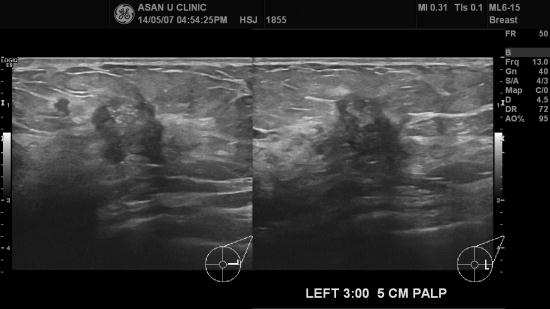

아산유외과 개원 후 97번째 유방암진단.

유방에 통증이 있어 내원한 46세 여성분입니다.

좌측 유방에 2cm이상의 미세석회화 포함된 결절 및

1cm전후의 결절들이 흩어져 있습니다.

조직검사상 침윤성 유관암 진단되셨습니다.

다발성 소견이라 유방MRI로 확인후 수술이 진행되실 겁니다.

40, 50대 이상의 여성에서 유방 통증이 있는 경우

유방의 건강을 점검해보세요.